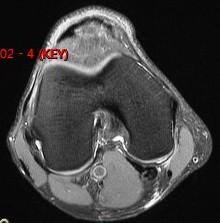

Figure 1 for case Semitendinosus tendon tear, retracted( RID2717 )

Figure 1